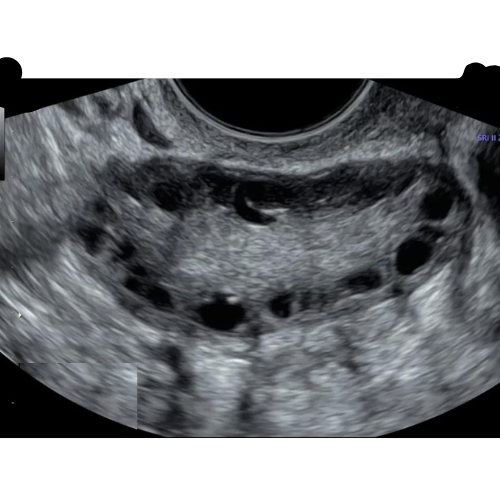

Advanced Gynecological Ultrasound for PCOS

Understanding PCOS Through Advanced Gynecologic Ultrasound Polycystic Ovary Syndrome (PCOS) can sometimes feel overwhelming with its many symptoms—irregular periods, acne,

Advanced Gynecological Scan for Endometriosis

Precision Imaging for Early Detection and Effective Management Endometriosis is one of the most complex gynecological conditions, often causing pelvic